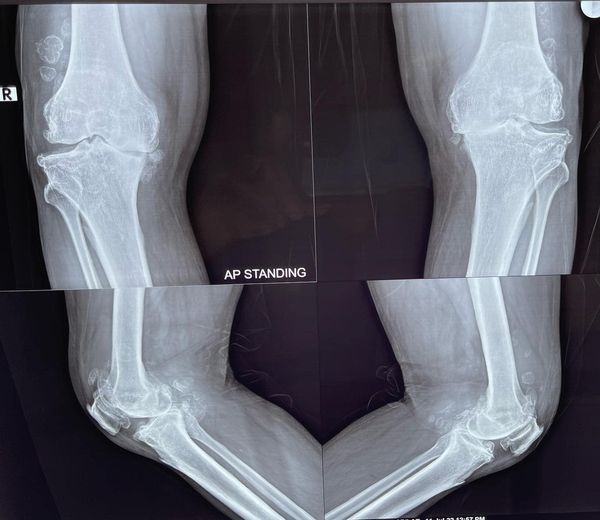

Some problems if ignored for fear or some other prejudice can cripple a person permanently, like this 65 yr old gentleman who can barely walk with this extremely deformed knee, correction of such a deformity can be challenging because of the inherent bone loss of nearly 15 mm that was discovered during surgery, however with the advent of swasthyasathi and other forms of medical insurances such surgeries are now can be done for free to give even people with less fortune a new breath of life. the total knee replacement knee deformity correction Monday surgery